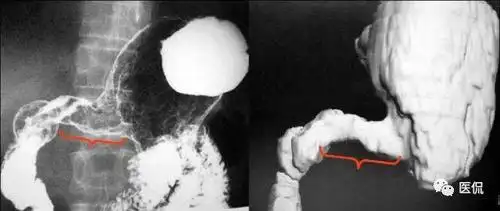

溃疡型:龛影大多成多角形;周围有清楚的环堤;周围皱襞中断,末段呈杵状

龛影位于胃轮廓之内,龛影外围绕以宽窄不等的透明带即 环堤,轮廓不

僵硬为特征溃疡型:龛影大多成多角形;周围有清楚的环堤;周围皱襞中断